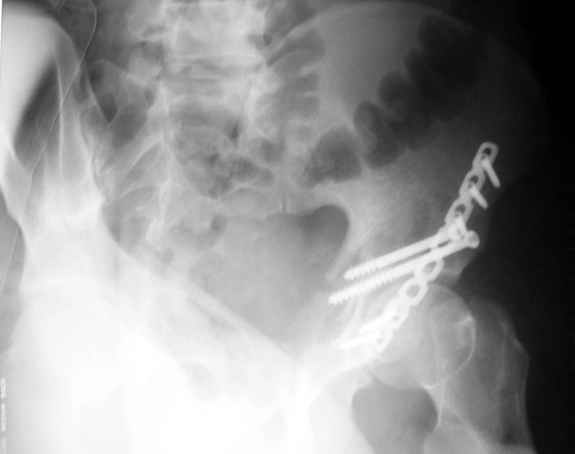

Не дождавшись советов, в понедельник прооперировал больного, заняло времени..., но все сделал в один этап: сначала фиксировал ипсилатеральный перелом бедра и шейки реконструктивным гвоздем Smith&Nephews, потом из расширенного илеофеморального доступа фиксировал перелом крыла подвздошной кости тягловым винтом, нейтрализующей пластиной заднюю колонну, и тягловыми винтами 3,5 мм переднюю колонну.

К сожалению, набора для ретроградного или антеградного реконструктивного штифтования в операционной нет, поэтому доставка заняла н-ное время. Вопрос, который возник у меня- по поводу оптимальной тактики хирургии: вся фиксация в один этап из расширенного доступа или последовательно сначала бедро и позже реконструкция впадины, комбинированный доступ к впадине отдельно к передней и задней колоннам или из расширенного илеофеморального одного доступа. Все-таки решил остановиться на одноэтапном подходе и спустя 5 дней (как раз и наборы привезли) из расширенного илеофеморального доступа сначала фиксировал реконструктивным штифтом Smith&Nephews бедро и

шейку (благо перелом шейки 2 типа -относительно стабильный) затем фрагмент крыла подвздошной кости Lag screw, далее пластина на заднюю колонну и винты в переднюю колонну.(с размерами и направлением винтов ошибка вышла:-((, но интраоперационно у меня была полная уверенность , что винты *ушли* в лонную кость).

Еще раз спасибо за комментарии и готовность помочь с имплантами. Постоп картинки в приложении,